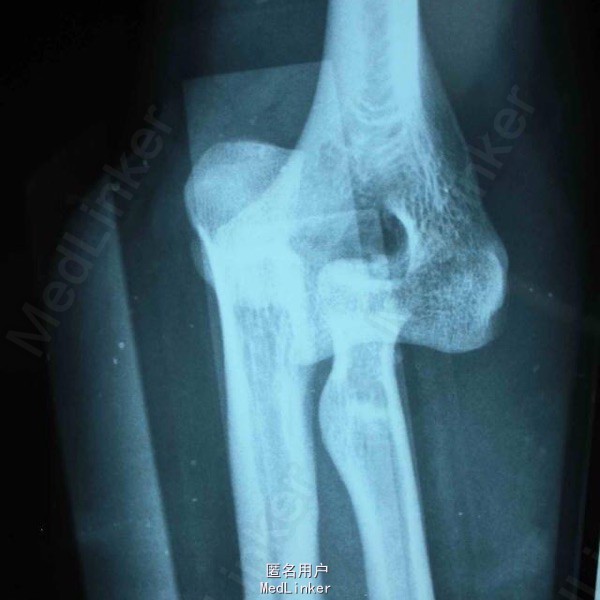

手法复位后X片及术后正侧位 初步诊断:左肘关节损伤三联征。治疗过程:尺骨冠状突骨折块复位固定、桡骨小头骨折块复位固定、内外侧副韧带修复、可活动式外固定支架固定。